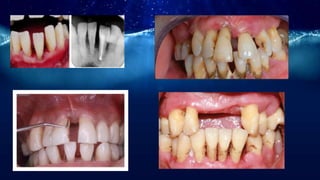

Aggressive periodontitis

• Aggressive periodontitis refers to the

multifactorial,severe and rapidly

progressive form of

periodontitis,which primarily but not

exclusively affects younger patients.

Diagnostic criteria

• 1-age

• 2-A distinctive radiography pattern depiciting vertical

alveolar bone loss at the first permanent molars and at one

or more incisor teeth.(classical case=an arc-shaped loss of

alveolar bone,extending from the distal surface of 5 to the

mesial surface of the 7)

• 3-Rapid progression

• 4-The disease affects only the permanent dentition.

• 5-The amount of local etiologic factors is not

commensurated with the severity of periodontal

destruction.

• 6-Black male>black female>white female>white male

• 7-In general female to male ratio is 3:1

• 8-Familial pattern

Generalized)

-generalized juvenile periodontitis or

rapidly progressive periodontitis

- Usually <30 yrs

-at least three permanent teeth other

than first molars and incisors

Localized)

-localized juvenile periodontitis(LJP)

-11-13 yrs

-Attachment loss on at least 2

permanent(one of which is a first molar)